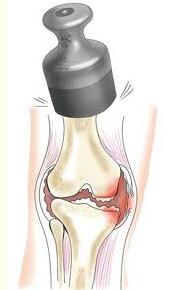

Коленный сустав человека находится под постоянной нагрузкой, удерживая вес тела человека и  обеспечивая большой объем движений ноги. Основным фактором возникновения артроза считается механический. Из-за микротравматизации суставного хряща и осевого давления на него в нагрузке - нарушается структура хрящевой поверхности. Образуется что-то подобное "пролежню" на самой нагружаемой поверхности хряща. Хрящевая ткань неоднородна и напоминает губку с очень тонкими порами. Благодаря своему строению и химическому составу, хрящ обеспечивает прочность, упругость и эластичность сустава. При движении, под действием веса тела суставной хрящ коленного сустава сдавливается как губка, а неиспользованная тканевая

обеспечивая большой объем движений ноги. Основным фактором возникновения артроза считается механический. Из-за микротравматизации суставного хряща и осевого давления на него в нагрузке - нарушается структура хрящевой поверхности. Образуется что-то подобное "пролежню" на самой нагружаемой поверхности хряща. Хрящевая ткань неоднородна и напоминает губку с очень тонкими порами. Благодаря своему строению и химическому составу, хрящ обеспечивает прочность, упругость и эластичность сустава. При движении, под действием веса тела суставной хрящ коленного сустава сдавливается как губка, а неиспользованная тканевая

жидкость выдавливается из него. При разгрузке давление в хряще падает и он, аналогично губке, освободившись от давления, расширяясь, всасывает в себя свежую, богатую питательными веществами синовиальную (суставную) жидкость.

Таким образом, при каждом шаге осуществляется питание хряща. Выражение «Движение - это жизнь» во всей своей полноте оправдано жизнедеятельностью гиалинового хряща. После нагрузки необходимо восстановление. За счет чего? В суставе нет сосудов. Питание хрящевой ткани осуществляется в большей степени за счет суставной жидкости (синовиальной), которую продуцирует суставная сумка. Все нужные для восстановления и регенерации вещества находятся в ней. Питание суставного хряща в меньшей степени происходит и благодаря сосудам субхондральной зоны эпифиза. И если сустав не успевает восстановиться до следующего момента перегрузки, возникает так называемый дистрофический процесс - нарушение питания.